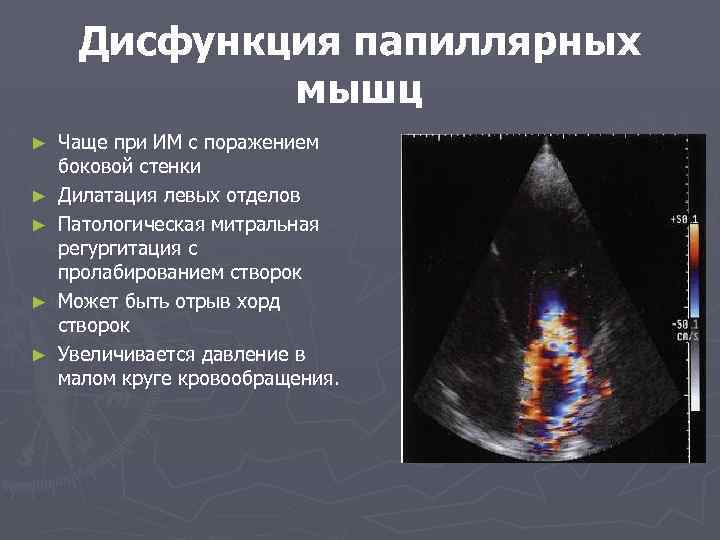

Дисфункция папиллярных мышц ► ► ► Чаще при ИМ с поражением боковой стенки Дилатация левых отделов Патологическая митральная регургитация с пролабированием створок Может быть отрыв хорд створок Увеличивается давление в малом круге кровообращения.